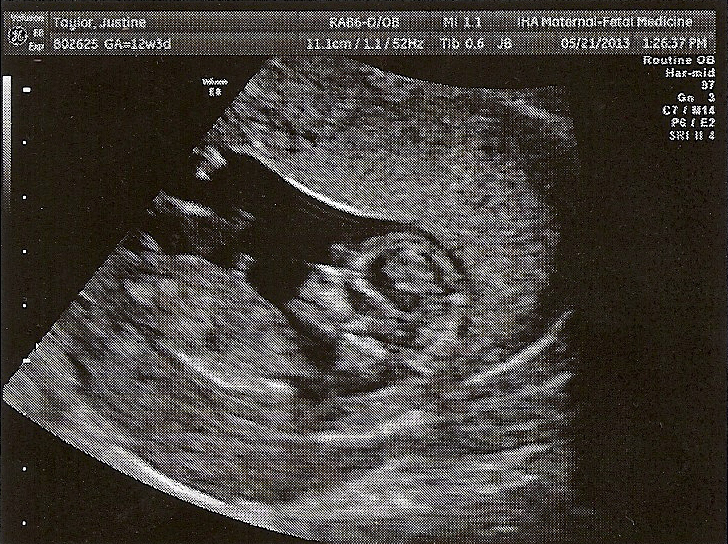

When I was twelve and a half weeks along, we went in for an intense ultrasound that was supposed to help determine our course of preventative treatment. Since things looked normal (as they always did with Lydia) we didn’t learn a whole lot from this one, but it was fun to see Baby again. Here she is, now just over 11 cm long (that’s almost 4 ½ inches):

One slight complication the ultrasound identified was that Baby’s umbilical cord is attached to the edge of the placenta, instead of being centered. From our best understanding, this usually doesn’t affect Baby, but there’s a “possibility”, say the doctors, that Baby could not get everything she needs through the cord to grow properly. The solution is to do lots of extra ultrasounds to see if she’s growing, and if not, deliver early. We’d rather not deliver early and certainly don’t plan on delivering so early that she couldn’t survive, so we have delayed these extra ultrasounds for the moment.